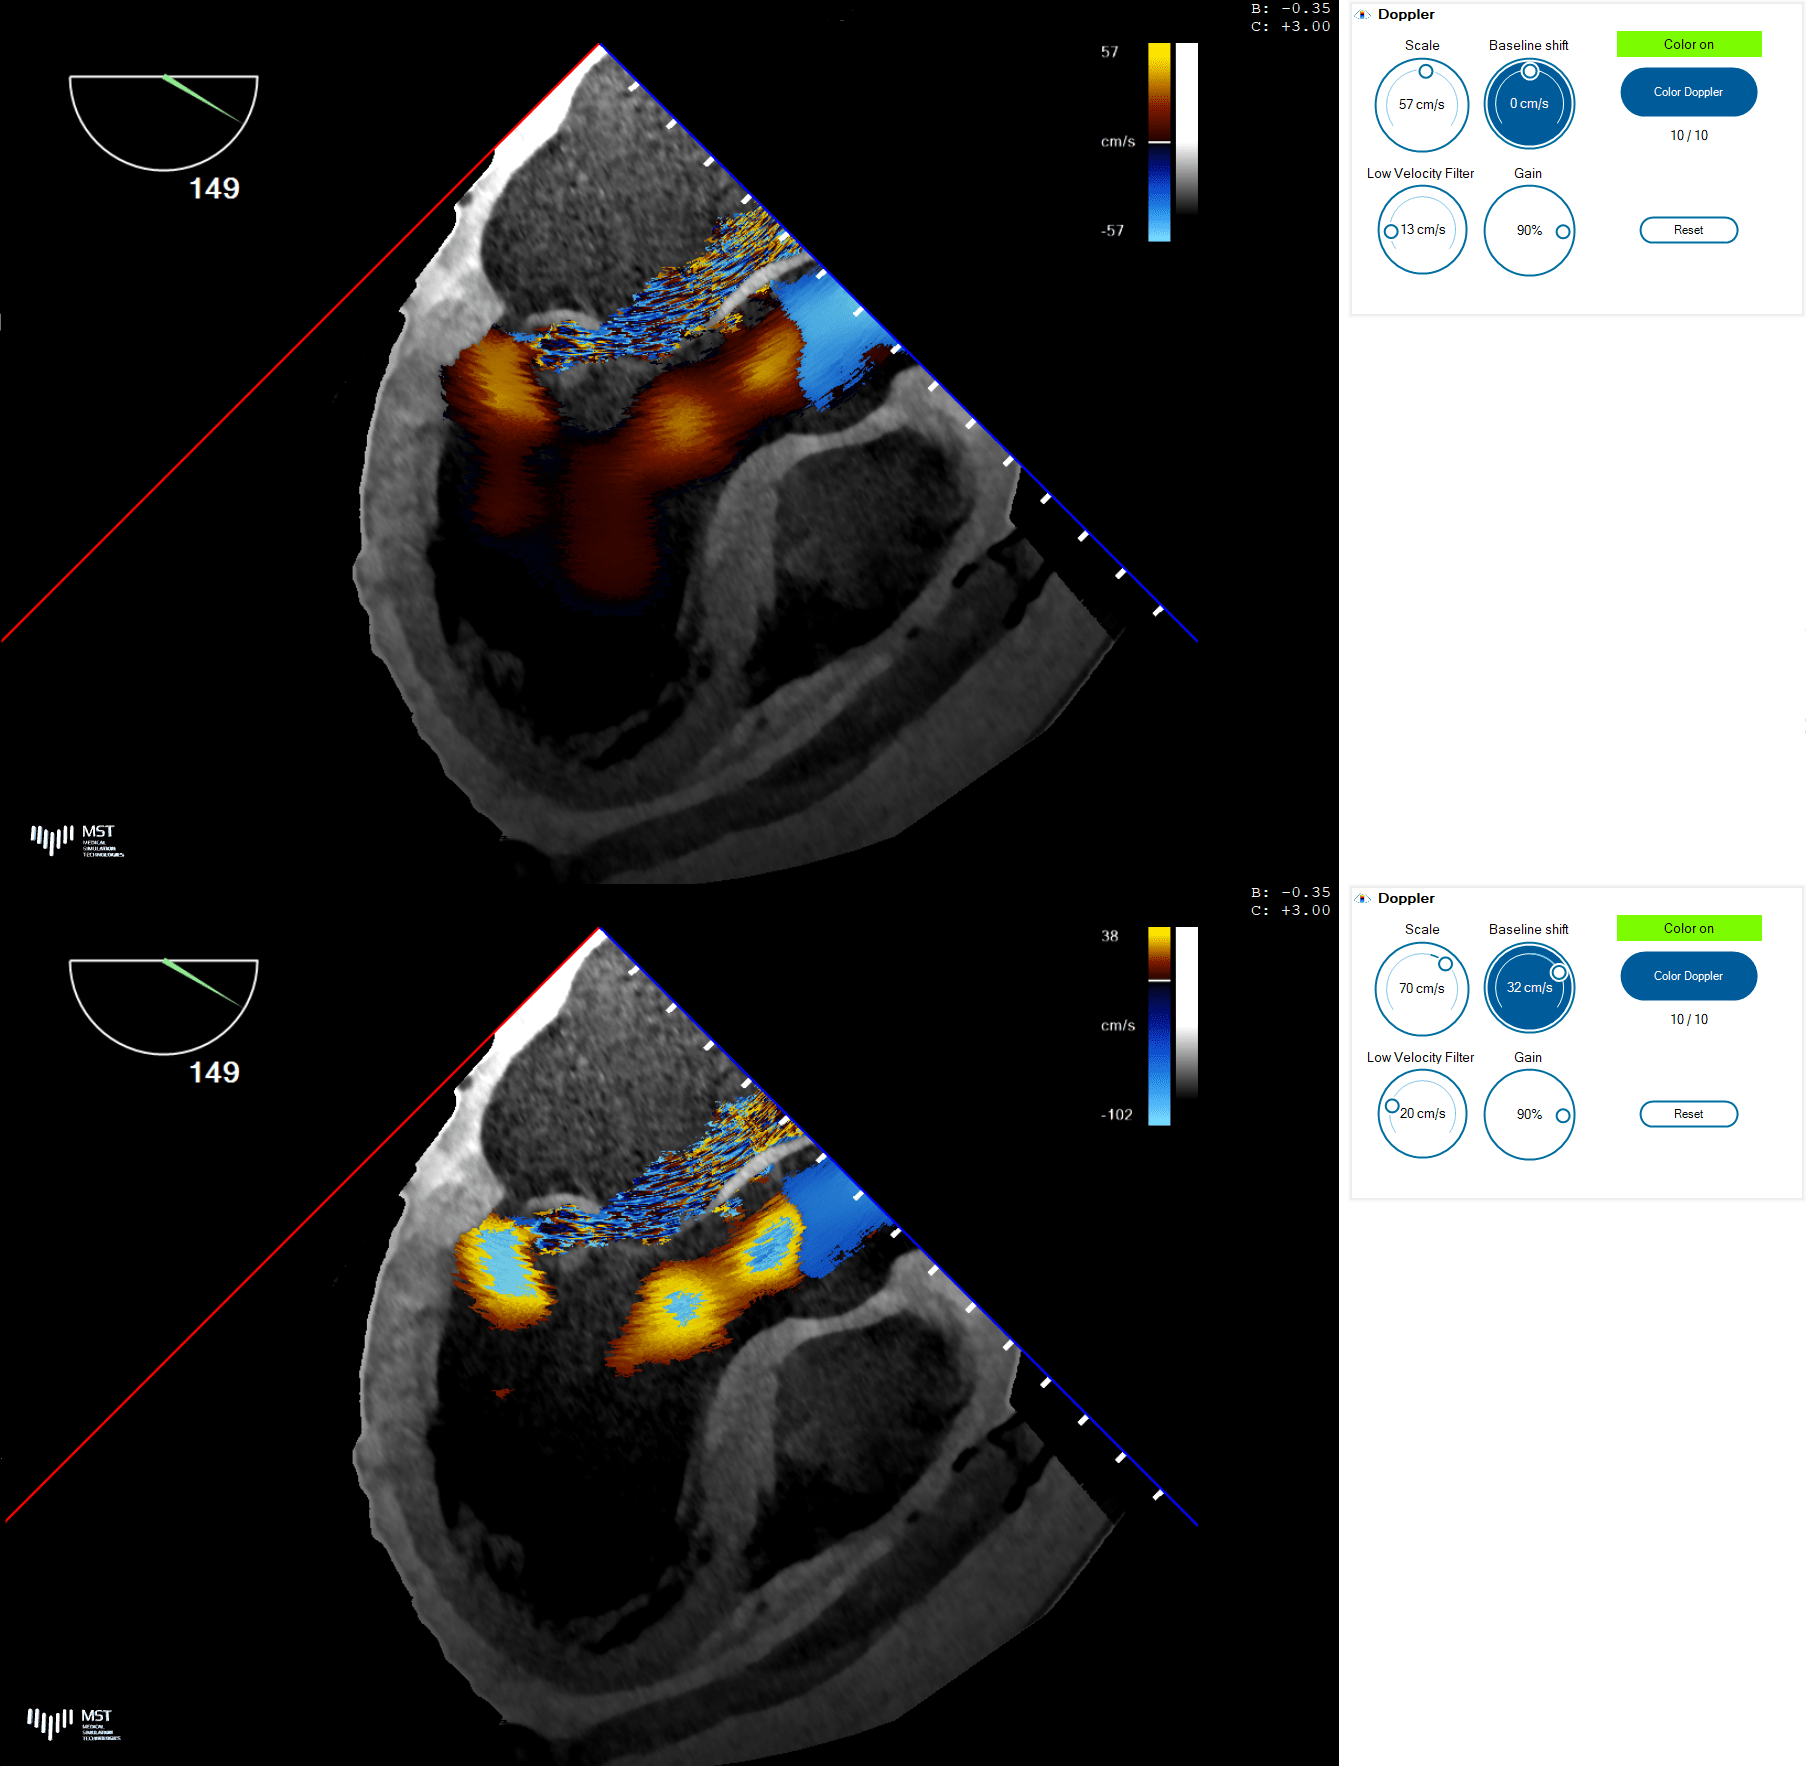

Doppler mode

The Doppler panel contains manipulators used to adjust the Doppler scale, baseline shift and low velocity filtering.